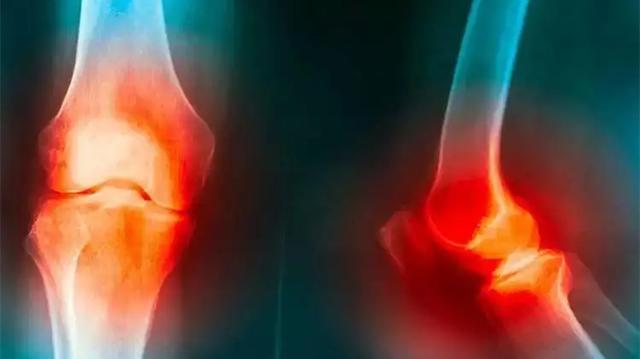

膝关节炎是一种以退行性病理改变为基础的疾患。发病的时候膝盖会出现红肿痛、上下楼梯疼痛、坐起立或行走时膝盖酸痛等症状。

比较严重的患者会出现肿胀、弹响、积液等情况,如若再不及时治疗,则会导致关节畸形、残废的可能。研究表明,老年骨关节炎的致残率可高达53%,且如若不及时防范,骨关节炎的过程是不可逆的,一旦损伤就不能自行恢复。